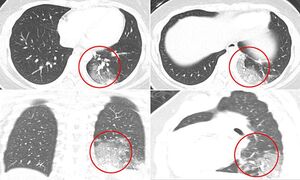

mshrgh.ir/1071375 کد خبر 1071375 تاریخ انتشار: ۲۲ اردیبهشت ۱۳۹۹ - ۰۸:۰۳ ۰ نظر چاپ عکس و فیلم عکس/ سی تی اسکن از کودکان مبتلا به کرونا تصاویر سی تی اسکن از کودکان مبتلا به کرونا در بوستون آمریکا نشان می دهد بیش از نیمی از آنها دچار التهاب شدید ریه هستند. اخبار مرتبط عکس/ تمرین ورزشکار قایقرانی در خانه فیلم/ اروپا در صف کیت تشخیص کرونای ایرانی فیلم/ آخرین آمار مبتلایان به کرونا در جهان عکس/ تمرین ورزشکاران ایرانی در شرایط کرونایی فیلم/ نکات کلیدی استفاده از ماسک در مترو عکس/ درگیری پلیس با مخالفان قرنطینه عکس/ تعظیم تکنولوژی، اینترنت و آموزش مجازی! عکس/ همافزایی گروههای جهادی در پویش ۱۴۴۱ عکس/ دیدار بستگان از طریق جرثقیل عکس/ به وقت افطار عکس/ تظاهرات معترضان به قرنطینه در آلمان عکس/ تب سنجی قبل از جلسه دادگاه عکس/ مقاومت یک کودک در برابر انجام تست کرونا عکس/ مرحله دوم کمک مومنانه در آذربایجان برچسبها ویروس کرونا کودکان سی تی اسکن بیماری ریه آمریکا